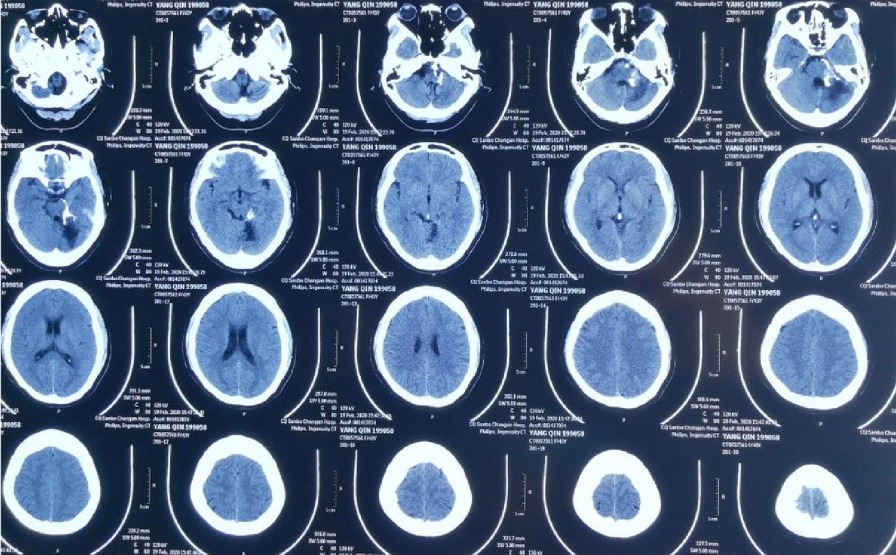

第⼀次CT显⽰:小脑出⾎,蛛⽹膜下腔出⾎,第IV脑室内出⾎

本次出⾎CT

⼊院CT显⽰:桥脑旁有出⾎